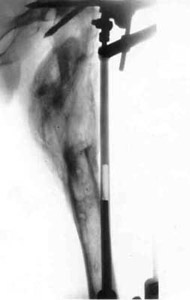

Results of treatment.Results of treatment.Results of treatment.